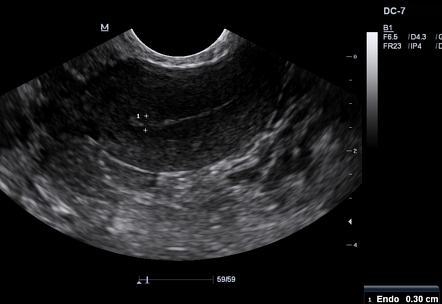

Endometrial Thickness What Is Normal And How To Measure .

Endometrial Thickness Radiology Reference Article .

Endometrial Thickness An Overview Sciencedirect Topics .

Sonohysterographic Measurement Of Endometrial Thickness .